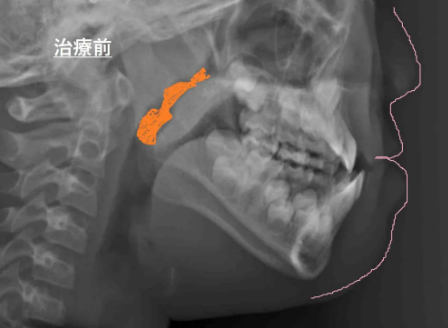

このレントゲンは、頭部X線規格写真(セファログラム)というもので、矯正治療を行う際に特に多く撮影されるものです。

要は、お顔全体の横顔の骨格をみています。

要は、上顎が成長してきています! - 気道が広くなっています!!!!(治療前はオレンジの部分、治療後は赤い部分。赤い部分が広くなっているのがわかりますか?ここが気道で、広いほうが呼吸がしやすいです!!!!)